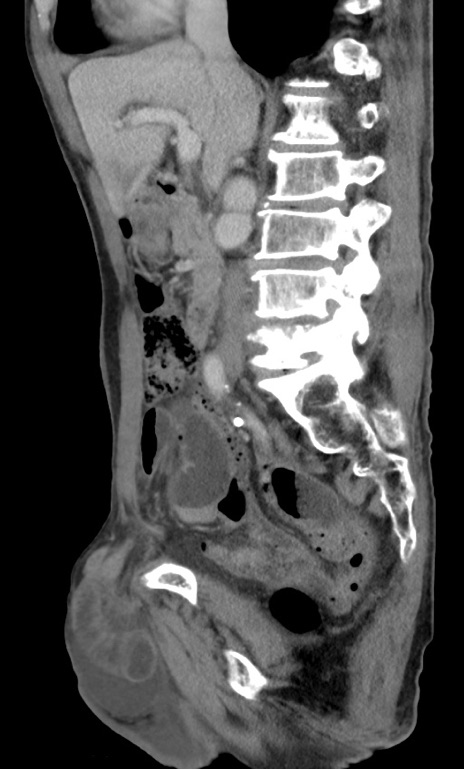

横断像

【症例】 70歳代男性

【主訴】右鼠径部腫瘤、疼痛

【現病歴】本日朝より上記主訴あり、受診。

【既往歴】膀胱癌にて膀胱全摘、両側尿管皮膚瘻

【データ】WBC 5600、CRP 0.56